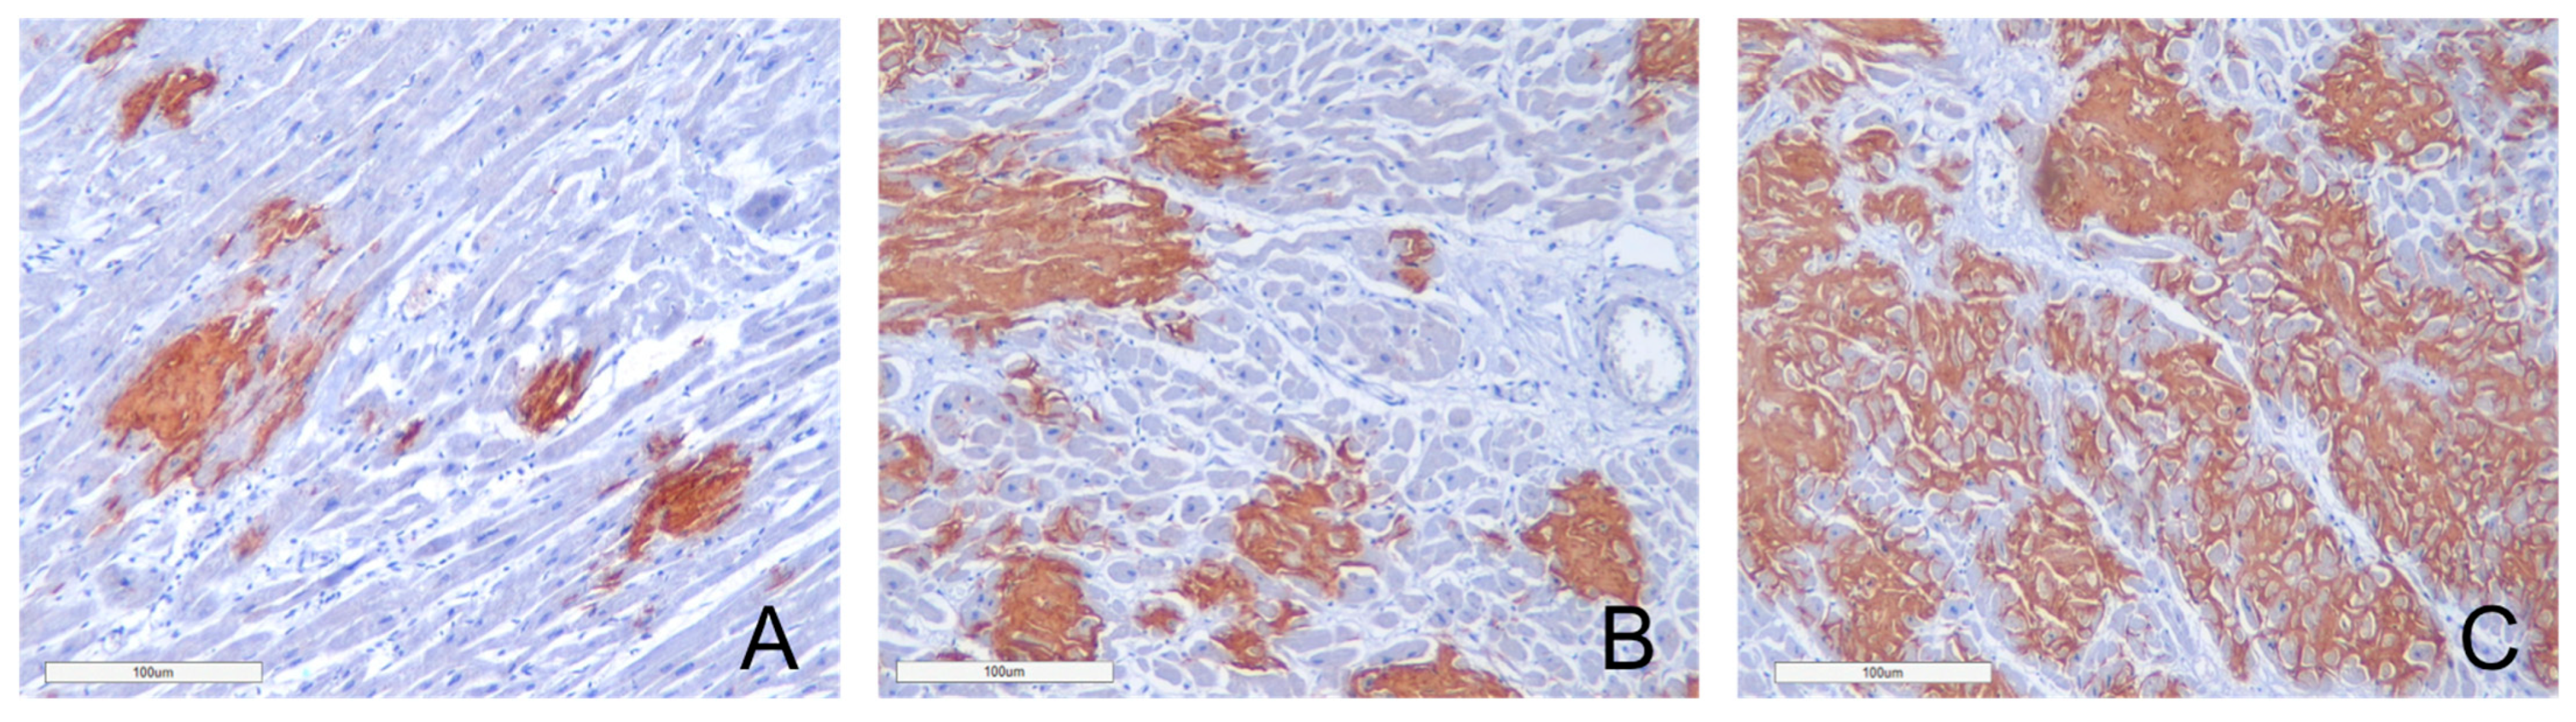

2.2. Immunohistochemical Typing of Amyloid